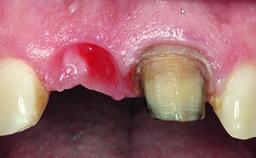

Replacement of an Upper Right Central Incisor with a Root Fracture, Early Placement of an RC Bone Level Implant, Variobase Abutment

A healthy 28-year-old female patient presented for a consultation on treatment options to restore her upper right central incisor. At the clinical examination, the tooth responded to percussion and palpation. The gingiva was red and slightly swollen, with a mid-facial probing depth of 10 mm. The upper right lateral incisor showed no signs or symptoms, did not respond to exploration and percussion, and the vitality test was positive. The periapical radiograph revealed that tooth 11 had been endodontically treated, with no lesion evident at the apex. A small radiopaque calcified structure surrounded by a narrow radiolucent zone (3 × 3 mm) was present at the apex of tooth 12.